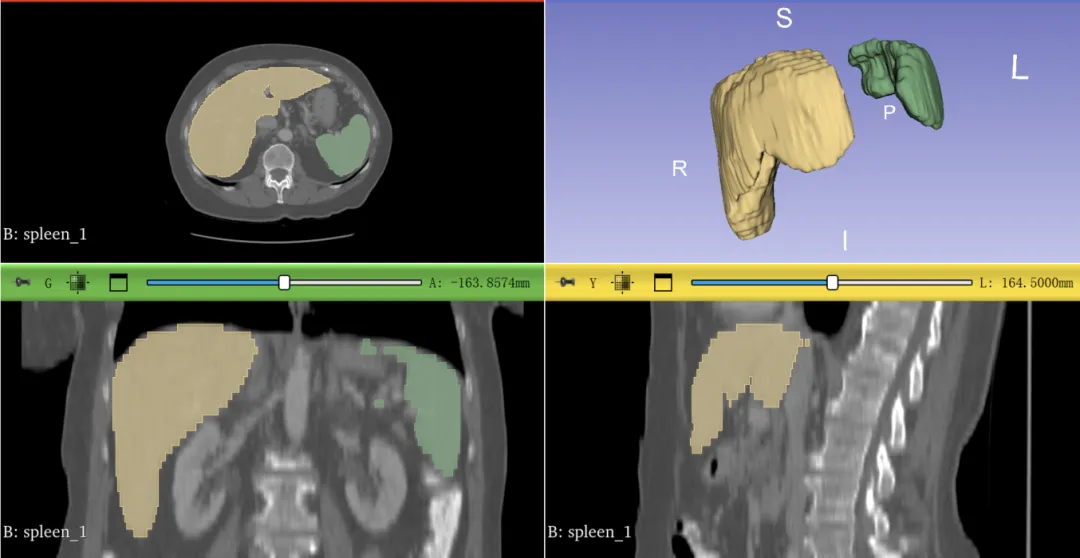

比如,上图里,我选择分割脾脏,肝脏,最后的结果就是只分割了这两个器官,不需要再手动删除不要的器官了~